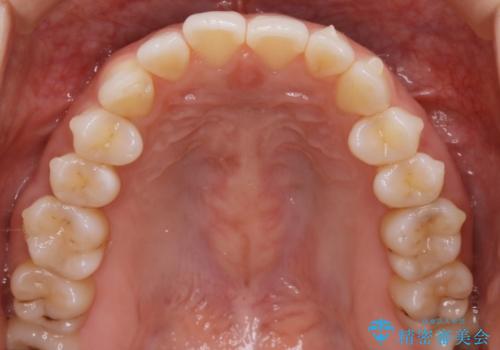

【非抜歯】前歯のガタつき マウスピースの部分矯正

- 上下の前歯の細かいガタつきの治療をご希望されて来院されました。

奥歯部分にはガタつきや噛み合わせの問題などがほとんど見られず、前歯のガタつきも軽度だったため、インビザライン ライト パッケージでの部分矯正を行うこととなりました。

今回のケースでは奥歯の噛み合わせに問題がほぼみられなかったため、前歯の位置のみに焦点を当て部分矯正を行いました。